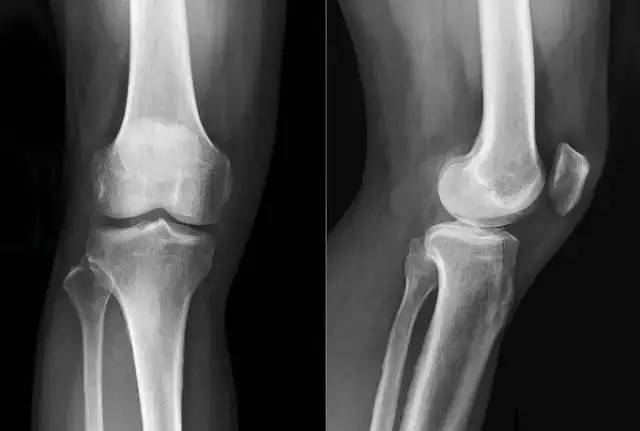

正常的膝关节片子

医:上图是您右膝的负重正、侧位片,下图是一组正常的膝关节片子。